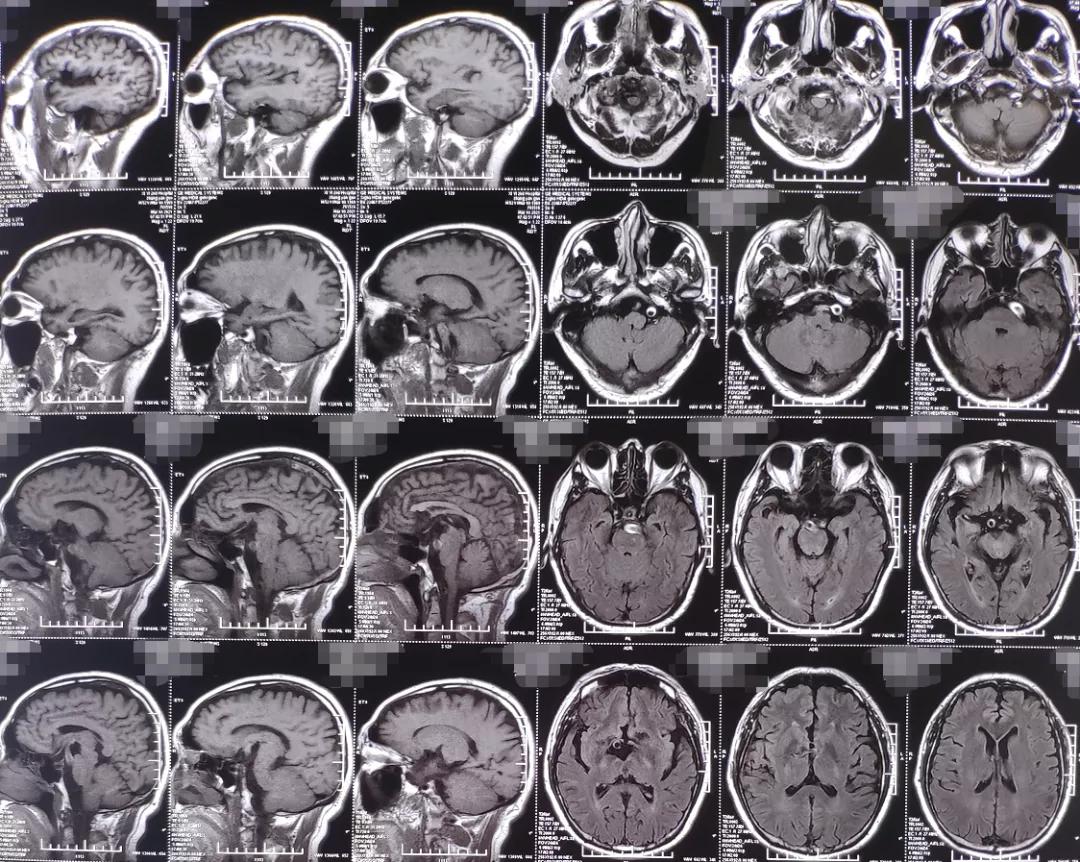

术前影像学检查: